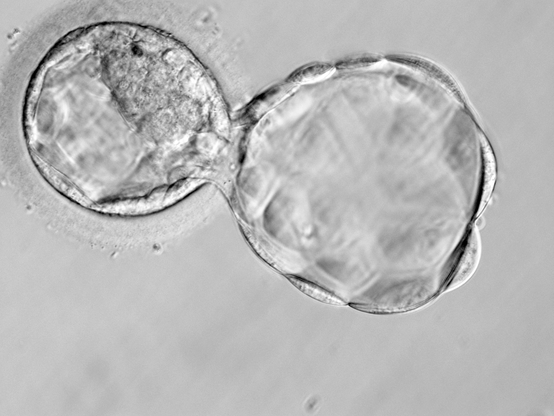

Ambos trabajos están relacionados con la transferencia de un embrión, logrando un verdadero impacto en la comunidad médica, ya que pocos centros en el mundo han logrado transferir un solo embrión y mantener excelentes resultados de embarazo.

- Análisis de la influencia del cambio en la expansión de blastocistos descongelados en las tasas de implantación (Autora: Lic. Cecilia Delpiccolo).